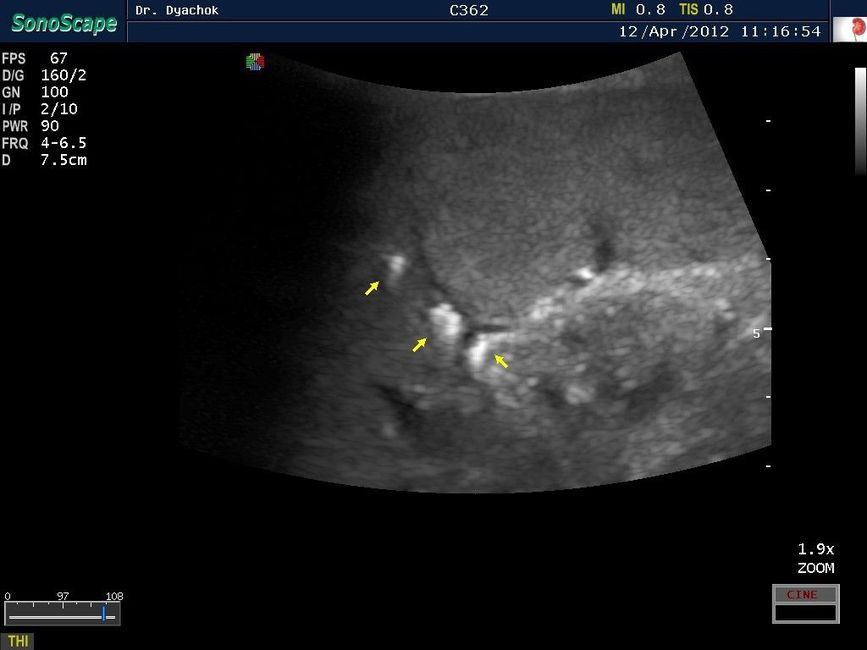

Sonoscape S9 представляет собой топовую переносную ультразвуковую систему, сочетающую инновационный дизайн, современные технологии визуализации и широкие диагностические возможности. Компактный аппарат экспертного класса подтверждает лидирующие позиции компании на рынке портативных ультразвуковых систем.

• Технология подавления спекл-шума MicroScan для повышения четкости изображения

• Исследования поверхностных и абдоминальных органов